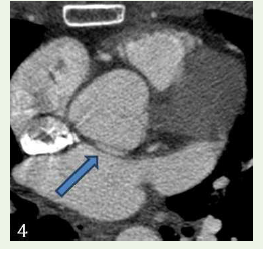

Case 4: A 68-year-old female with c/o chest pain, case of hypercholesterolemia and diabetes and concentric le ventricular hypertrophy in echocardiogram, demonstrated an anomalous origin of Left circumflex artery from the right coronary sinus with retro- aortic course.

Figure 4:Maximum intensity projection reconstruction shows anomalous

origin of left main coronary artery from non-coronary cusp with retro-aortic

course.

Figure 5:Maximum intensity projection reconstruction shows anomalous